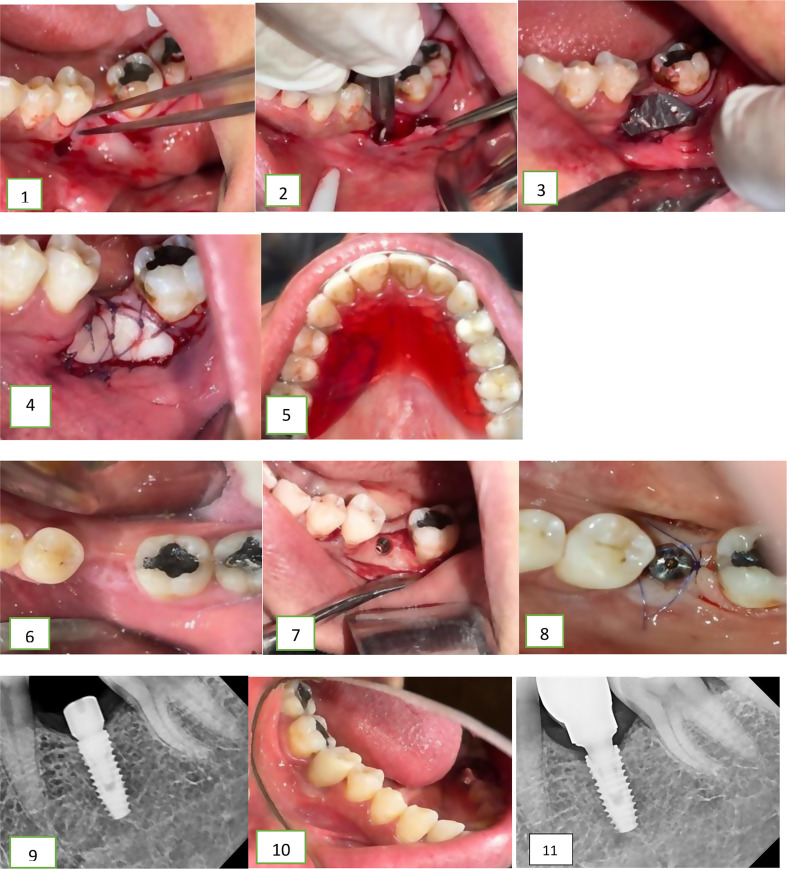

Purpose: This study measures the impact of timing of free gingival graft (FGG) in improving aesthetics, function, and long-term stability of dental implants by measuring keratinized mucosa width (KMW), soft tissue thickness (STT), and graft shrinkage after implant treatment.

Methods: The current randomized clinical trial included 20 patients with inadequate KMW and requiring placement of dental implant. The participants were randomly distributed into two groups. Group 1 received FGG 2 months before placing the dental implant while group 2 received the FGG at the second stage of implant surgery. The following parameters were evaluated and statistically analyzed at baseline, day 7, as well as 1, 3, 6, and 9 months postoperatively, KMW, STT and shrinkage percentage of the FGG.

Results: Twenty patients with ages ranging from 30 to 55 years with reduced KMW were included in the current study. Both groups showed a significant increase in KMW and STT on day7, 1, 3, 6, and 9 months postoperatively while the intergroup comparison showed no significant differences in KWM, STT, and shrinkage percentage between both groups at the same point of time.

Conclusion: The two study groups' outcomes demonstrated that the FGG can be placed either before or after dental implants to improve the soft tissue augmentation surrounding the implants. However, the implantologist should take patient preferences and long-term stability into consideration.